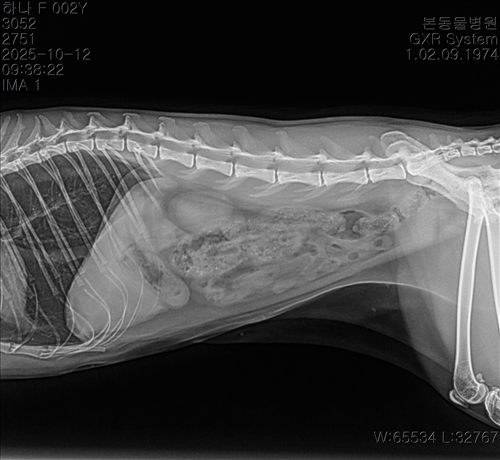

10.10/10.12/10.14일 엑스레이입니다

10월 10일 포도를 토해논후로 식욕저하 기력저하가 있어서 동물병원에 방문해서 엑스레이를 찍었는데 우선 지켜보자는 말과 소화제처방과 주사를 맞고 집왔습니다 그 후로도 안먹어서 12일에 동물병원에가서 혈액검사도 하고 수액도 맞았습니다 췌장쪽 수치가 좀 높아서 췌장쪽만 다시 검사했는데 수치는 괜찮았습니다 식욕촉진이랑 소화제처방 받아서 먹이는데 식욕저하도 여전하고 기력이 좀 없고 10일부터 14일까지 대변을 못보고있어서 14일에 병원에 가서 엑스레이랑 초음파를 했는데 장폐색일수도 있다는 말을 들었습니다 초음파상으로는 소장쪽 이물이 의심된다고 하셨어요ㅠ